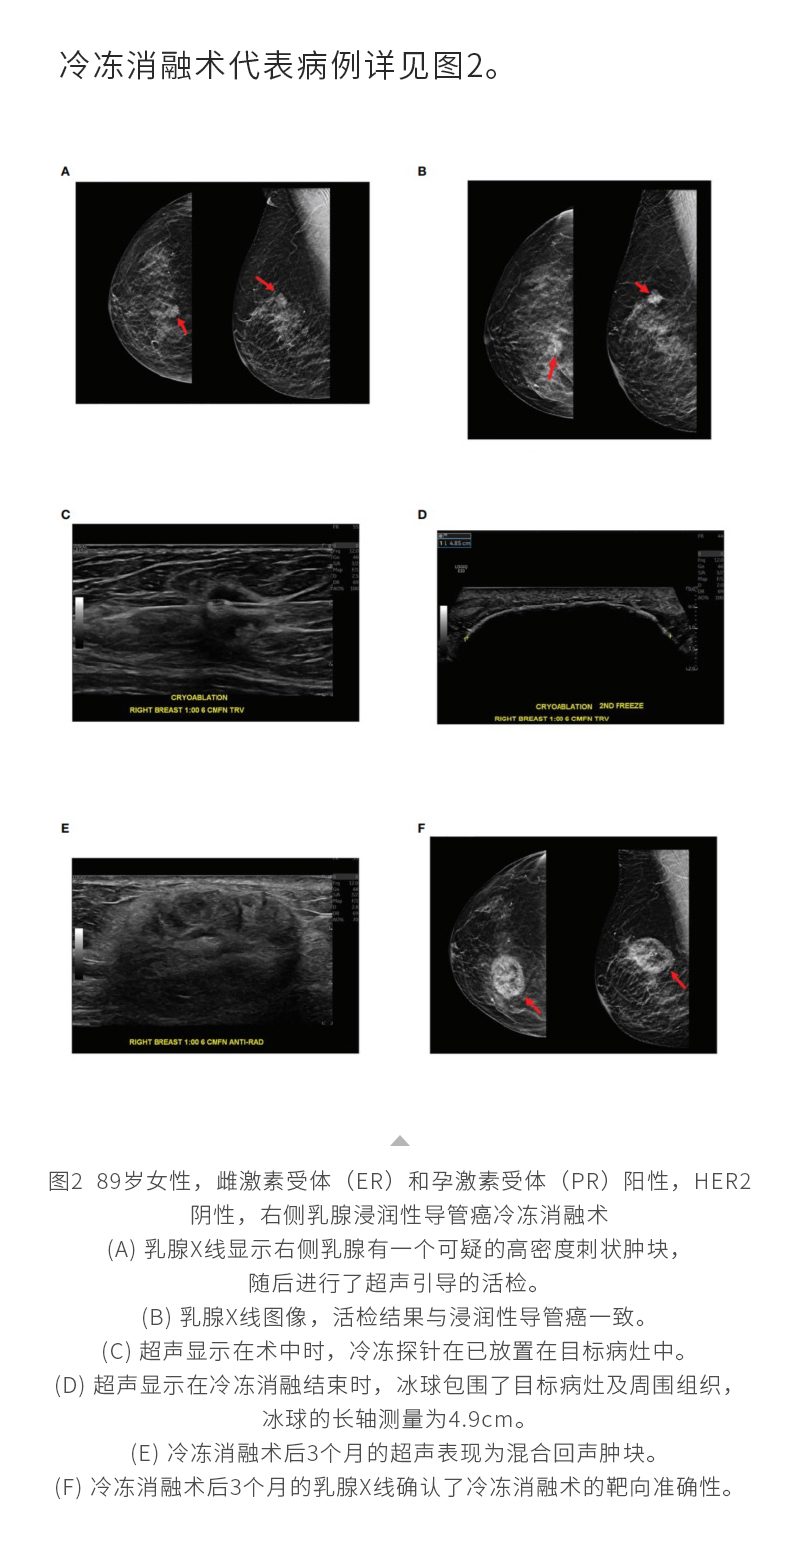

冷凍消融乳腺癌——【海杰亞科研資訊】第287期

發(fā)布時(shí)間:2024-10-28 | 作者:海杰亞 | 瀏覽次數(shù):1080